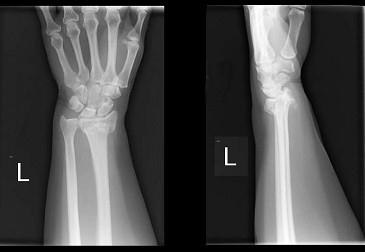

图示骨折,以下那种情况最少见 ( )A、合并腕三角软骨盘破裂B、合并下尺桡关节脱位C、骨折不愈合D、合并尺骨茎突骨折E、骨折畸形愈合

问题 图示骨折,以下那种情况最少见 ( )

选项 A、合并腕三角软骨盘破裂 B、合并下尺桡关节脱位 C、骨折不愈合 D、合并尺骨茎突骨折 E、骨折畸形愈合

答案 C